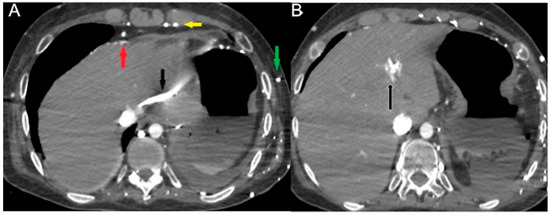

In contrast to horizontal levelling in the IVC layering sign, a vertical IVC levellng sign usually occurs due to physiological retrograde filling of renal veins [68]. Contrast stasis in the right-side cardiac chambers may result in extremely dense chambers and pulmonary arteries with or without a blood contrast level. Vascular stasis will also result in contrast layering within the veins that eventually drain into the right atrium (e.g., brachiocephalic and subclavian veins) (Figure 4).

Figure 4.

CECT images in obstructive shock in a severely dyspneic 28-year-old man with malignant pulmonary artery sarcoma. Arterial (A) and delayed (B) phase axial images show massive pulmonary trunk (black arrow) and right main artery (white arrow) soft tissue mass obstruction. A more caudal (C) axial image shows CM stasis in right cardiac chambers, no hepatic enhancement, and mild pleuropericardial effusion. (D) Delayed phase (delay of 200 seconds after CM injection) coronal reconstruction shows a thinned flat IVC (black arrow).